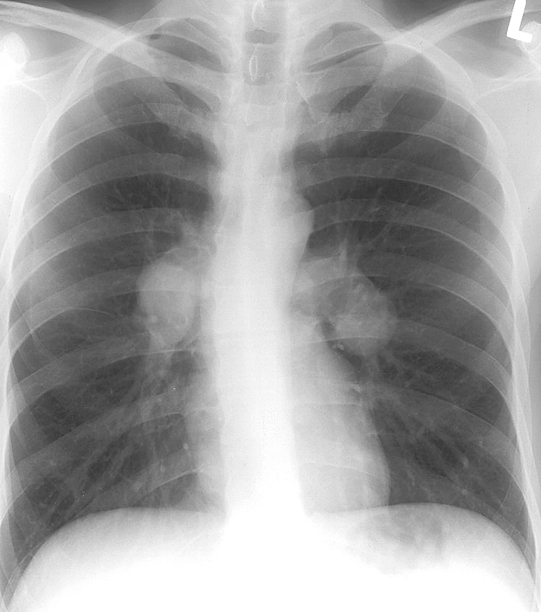

Gallery Mediastinum Lymphoma 1a

1a